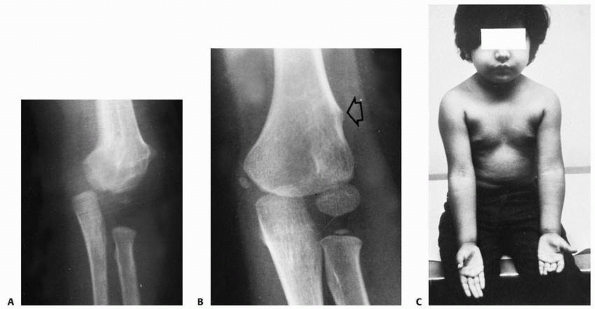

![]() |

FIGURE 15-13 Osteonecrosis of the lateral condyle after lateral condylar fracture in a 10-year-old boy. AP (A) and lateral (B) radiographs.

|